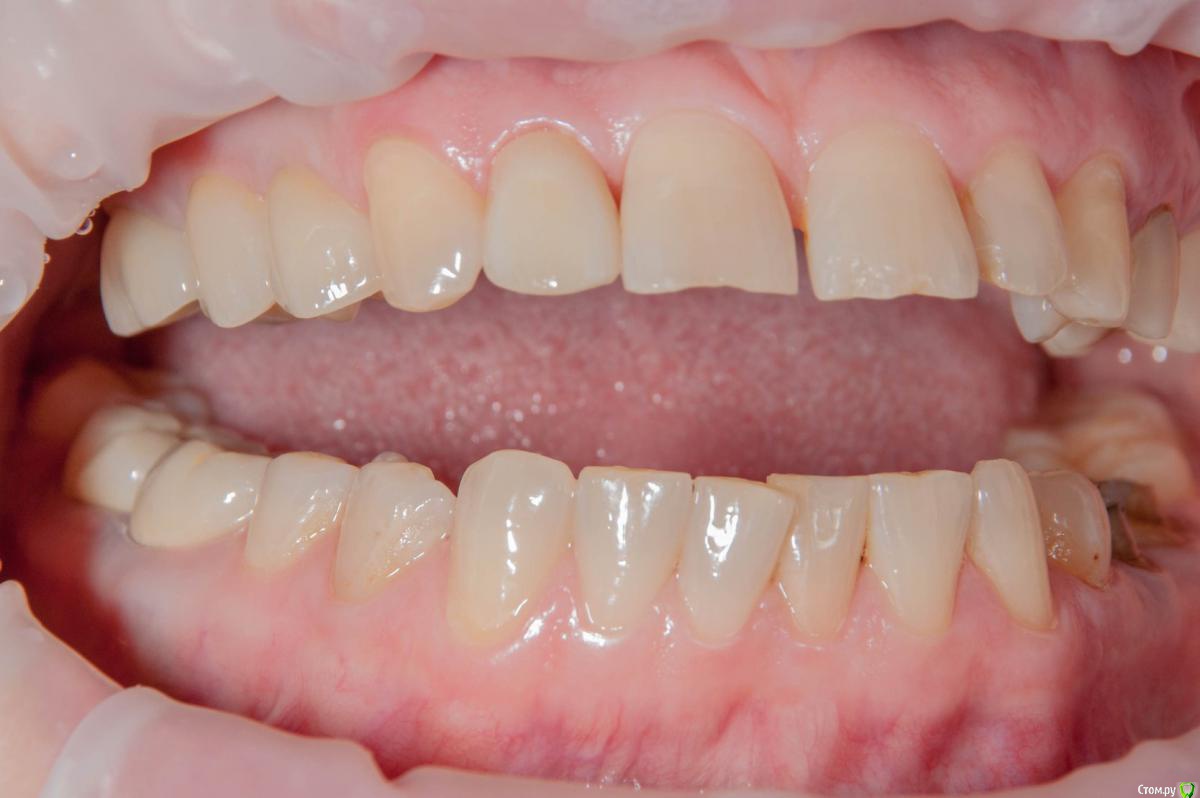

kamranchick Опубликовано 15 ноября, 2018 Поделиться Опубликовано 15 ноября, 2018 Без ССТ, Без Графта. торк 15, нагрузка в течении 8 часов.по последним моим наблюдениям, самое важно это 3д позиционирование имлпнатта, при правильном позиционировании, можно без всех штучек получить приемлимый долгосрочный результат. 5 Ссылка на комментарий

kamranchick Опубликовано 15 ноября, 2018 Автор Поделиться Опубликовано 15 ноября, 2018 Красиво .опишите условия при имплантации - одномоментно сразу после удаления зуба , отсрочено, возраст пациента ...?отлом зуба под десну, одномоментно сразу, женщина, 55 лет 1 Ссылка на комментарий

kamranchick Опубликовано 15 ноября, 2018 Автор Поделиться Опубликовано 15 ноября, 2018 Яйки как у всех)Пациентка мне очень импонировала если честно.Ну и преподаватель в вузе)Ну и двойка, не центральный резец))Тоже были фейлы, теперь минимум на 25 ставим временную коронку 3 Ссылка на комментарий